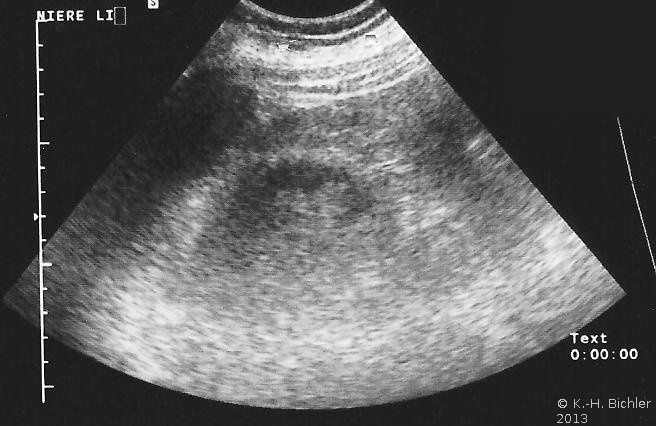

In der Sonographie fand sich eine kleine Niere links bei unauffälliger rechter Niere (Abbildung 18b).